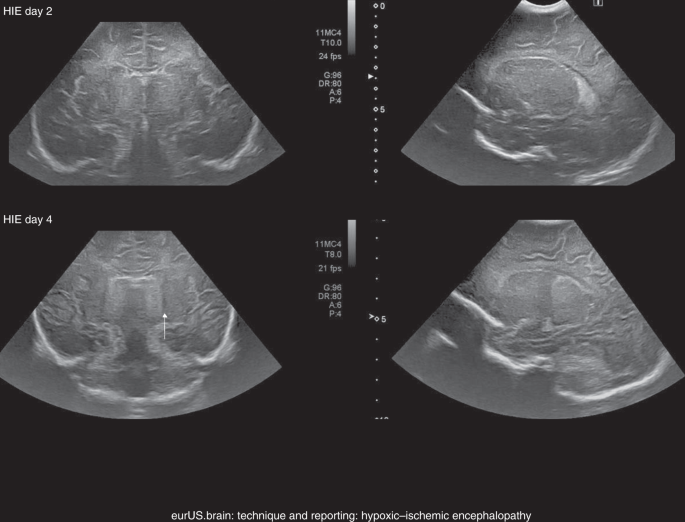

State Of The Art Neonatal Cerebral Ultrasound Technique And Reporting Pediatric Research